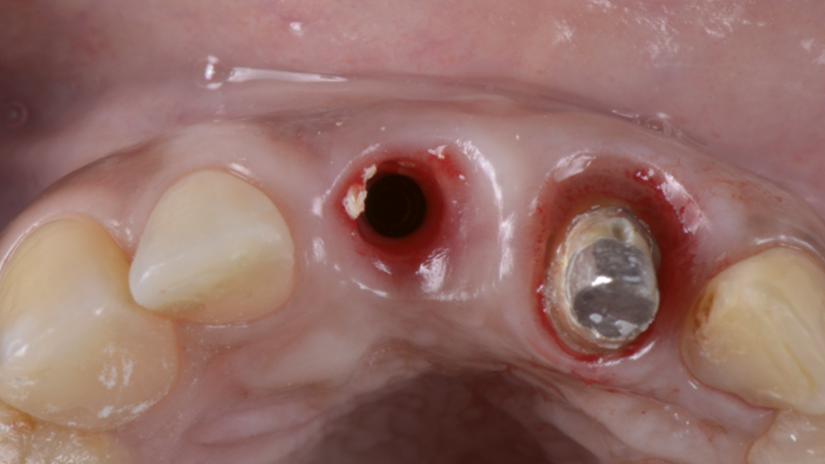

A paciente apresentava queixas estéticas e funcionais. Após avaliação clínica e radiográfica, optou-se pela substituição do pilar reto por um pilar Ideale angulado de 17 graus e 3,3 mm de diâmetro. Esse componente mais estreito e angulado permitiu corrigir o eixo emergente da futura coroa, viabilizando o planejamento de uma prótese parafusada na região estética.

O caso foi conduzido com planejamento cuidadoso, moldagens analógicas e provas clínicas. A reabilitação foi finalizada com a instalação de uma coroa metalocerâmica parafusada, garantindo estética, funcionalidade e reversibilidade do conjunto protético.